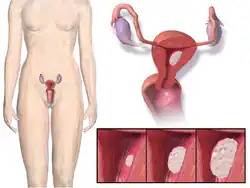

Endometrial cancer

In postmenopausal women, continuous combined estrogen plus progestin decreases endometrial cancer incidence.[51] The duration of progestogen therapy should be at least 14 days per cycle to prevent endometrial disease.[52]

Endometrial cancer has been grouped into two forms in the context of hormone replacement. Type 1 is the most common, can be associated with estrogen therapy, and is usually low grade. Type 2 is not related to estrogen stimulation and usually higher grade and poorer in prognosis.[53] The endometrial hyperplasia that leads to endometrial cancer with estrogen therapy can be prevented by concomitant administration of progestogen.[53] The extensive use of high-dose estrogens for birth control in the 1970s is thought to have resulted in a significant increase in the incidence of type 1 endometrial cancer.[54]

Paradoxically, progestogens do promote the growth of uterine fibroids, and a pelvic ultrasound can be performed before beginning HRT to make sure there are no underlying uterine or endometrial lesions.[53]

Androgens do not stimulate endometrial proliferation in post menopausal women, and appear to inhibit the proliferation induced by estrogen to a certain extent.[55]

There is insufficient high‐quality evidence to inform women considering hormone replacement therapy after treatment for endometrial cancer.[56]